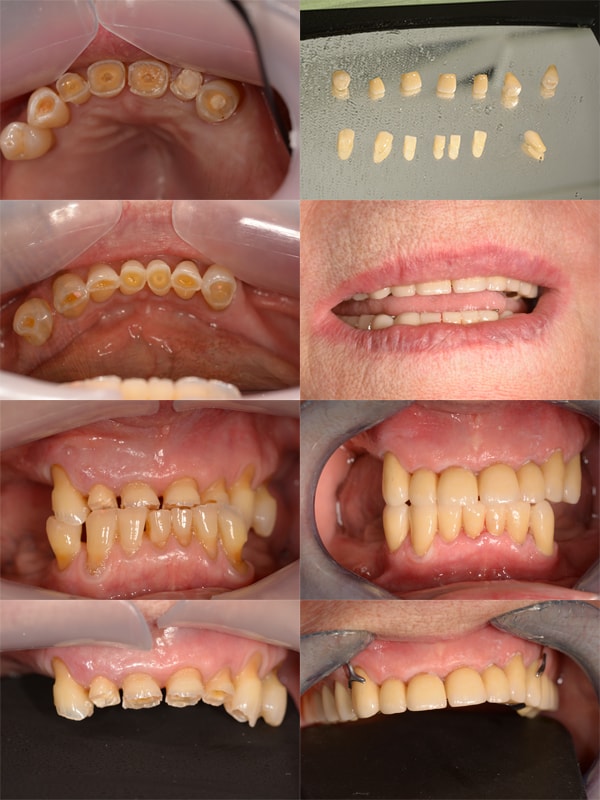

Les Usures

L’usure des dents n’est pas une maladie. Mais ce symptôme, de plus en plus fréquent et le plus souvent lié à notre hygiène de vie (alimentation, stress) et à des habitudes agressives de brossage, est difficile à prendre en charge. C’est pourquoi détecter précocement l’usure dentaire permet de corriger les facteurs aggravants.

L’usure des dents peut avoir une ou plusieurs origines.

Une origine mécanique :

L’utilisation d’une brosse à poils trop durs ou un brossage trop vigoureux qui peuvent entrainer un phénomène d’usure de l’émail.

Un brossage des dents réalisé immédiatement après avoir consommé des aliments acides.

Le bruxisme (grincer ou serrer les dents l’une contre l’autre)

Une origine chimique (on parle alors d’érosion), liés à la présence d’éléments acides dans la bouche :

La consommation excessive d’aliments ou de boissons acides tels que les sodas, l’alcool, les agrumes ou les sauces à base de vinaigre. Les médicaments comme la vitamine C ou l’aspirine dont l’acidité attaque les dents. Mais aussi certains antidépresseurs qui entrainent une réduction de la production de salive, protectrice naturelle des dents contre les attaques acides.

Certaines pathologies entrainant des vomissements et des reflux gastro-œsophagiens.

Le traitement passe tout d’abord par l’arrêt des “mauvaises” habitudes induisant les usures. Parfois il faut plusieurs séances pour que le patient trouve de quelle habitude il s’agit !

L’objectif ensuite est de protéger les dents dont l’émail a disparu en étant le plus conservateur possible ,c’est à dire en mutilant le moins possible la dent. En fonction de la sévérité de l’atteinte, les matériaux et les techniques différeront.On utilisera le plus possible des matériaux collés: des composites directs, des inlays, des overlays, des onlays, veneerlays, facettes ...